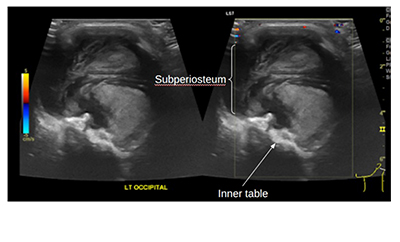

• Hemophilic pseudotumor of the skull: A rare presentation in a young child

Law Zhi Hou, M.D., Barbara Li Lian Kuok, Mrad., Normawati Mat Said, M.D.

230-239